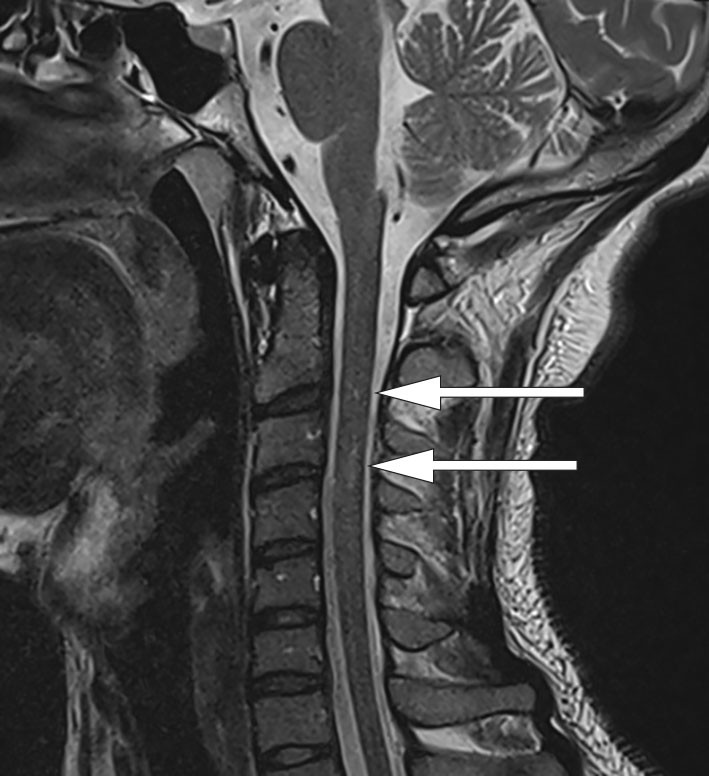

On contrast-enhanced MRI of the central nervous system on day 5, a sagittal section of a T2-weighted image showed a subtle high signal intensity in the spinal cord at C2/C3 (Figure 1), and an axial section showed contrast accumulation at the dorsal column (Figure 2). However, there was no uptake of contrast along lumbar nerve roots or the conus medullaris.

The findings indicated nerve injury in both the spinal cord and lower limbs. With a non-elevated protein level in the cerebrospinal fluid and no contrast accumulation in the lumbar area on MRI, the findings were not consistent with Guillain-Barré syndrome. MRI of the spinal cord (Figure 2) revealed a so-called inverted V or 'rabbit ears' sign. This is referred to as subacute combined degeneration and is characteristic of demyelination of the dorsal column caused by vitamin B12 deficiency (5).